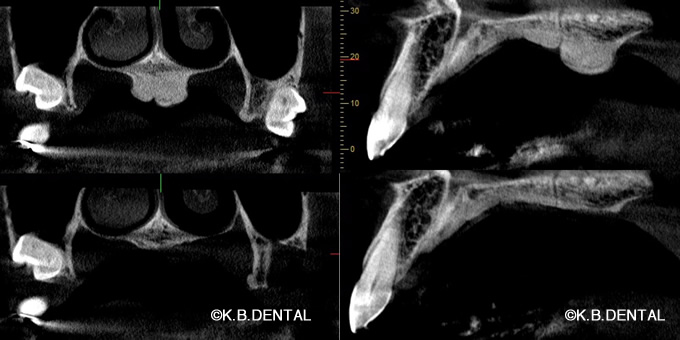

正中過剰埋伏歯(せいちゅうかじょうまいふくし)

正中過剰埋伏歯 症例

正中過剰埋伏歯の症例です。鼻腔底直下にあるので、静脈内鎮静を使い無痛抜歯で対応しました。抜歯が怖い方はご相談下さい。